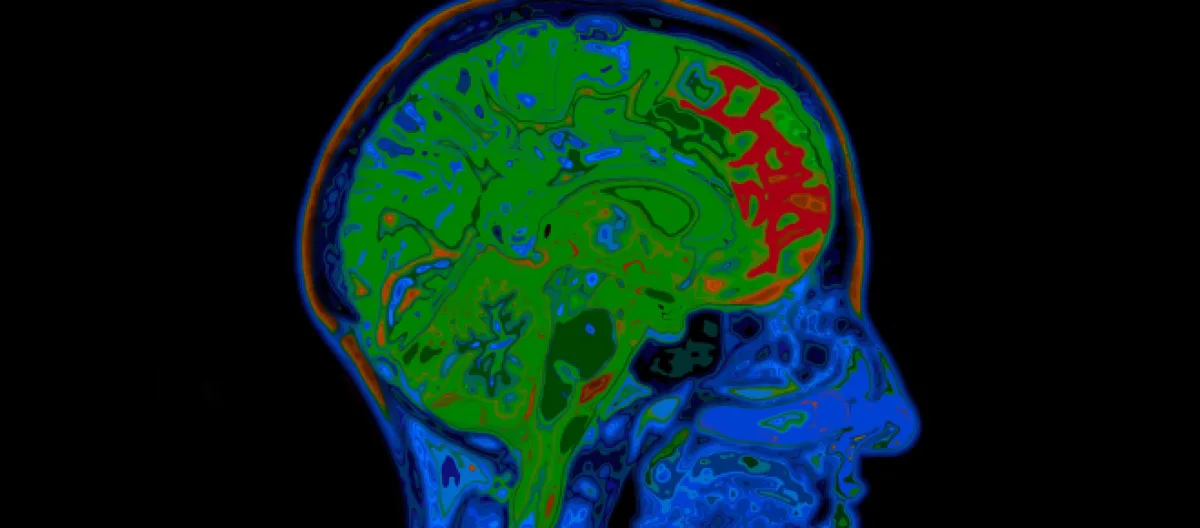

De acordo com os resultados, o SARS-CoV-2 pode de fato infectar o cérebro, em especial os astrócitos, que são as maiores e mais numerosas células encontradas no sistema nervoso central. Os pesquisadores explicam que a infecção das células levou a alterações no metabolismo e afetou o funcionamento de neurônios e neurotransmissores.

Ainda segundo estudo provisório, que ainda não foi avaliado pelos pares, até mesmo pessoas que desenvolveram formas leves da Covid-19, apresentando pouca ou nenhuma dificuldade respiratória, apresentaram alterações no córtex.

O córtex é a área em que se concentra a maior parte dos neurônios, comandando funções como a memória, a linguagem, a concentração e até mesmo a consciência. A alteração em sua espessura, provocada pelo vírus, poderia explicar porque algumas sequelas são persistentes em indivíduos que contraíram a doença.

A pesquisa também contou com exames realizados em 81 voluntários na Faculdade de Ciências Médicas (FCM) da Unicamp. Todos eles contraíram formas leves da doença e já haviam se recuperado na ocasião em que foram submetidos a uma ressonância magnética.

Os exames foram conduzidos cerca de 60 dias após as pessoas terem recebido diagnóstico positivo de contaminação, sendo que um terço deles relataram ainda ter algum sintoma neurológico ou neuropsiquiátrico. A maior parte dos indivíduos disse ainda sentir dor de cabeça ou fadiga. Entre as sequelas estavam também alteração da memória, perda de olfato, ansiedade, sonolência durante o dia, depressão, perda de paladar e até perda de libido.